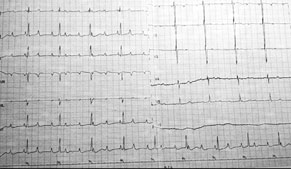

El electrocardiograma mostrará frecuencia atrial aumentada, frecuencia ventricular baja y ritmo de la unión o del nodo auriculoventricular de escape o ectópico. Puede encontrarse bloqueo auriculoventricular de primer o segundo grado que posteriormente se convertirá en completo. Hasta 40% de los bloqueos auriculoventriculares completos congénitos pueden no manifestarse hasta la niñez. Esto tal vez se debe a que pueden presentarse de forma intermitente y asintomática. En esta situación es muy poco probable que la causa sea el síndrome lúpico neonatal.12,13

A su ingreso a UCIN con facies características de síndrome de Down y síndrome de dificultad respiratoria que ameritó progresión a fase III de ventilación. A nivel hemodinámico precordio hiperdinámico, ruidos cardiacos arrítmicos, desdoblamiento del segundo ruido, frecuencia cardiaca de 65 lpm. Se realizó electrocardiograma y radiografía (figuras 1 y 2).